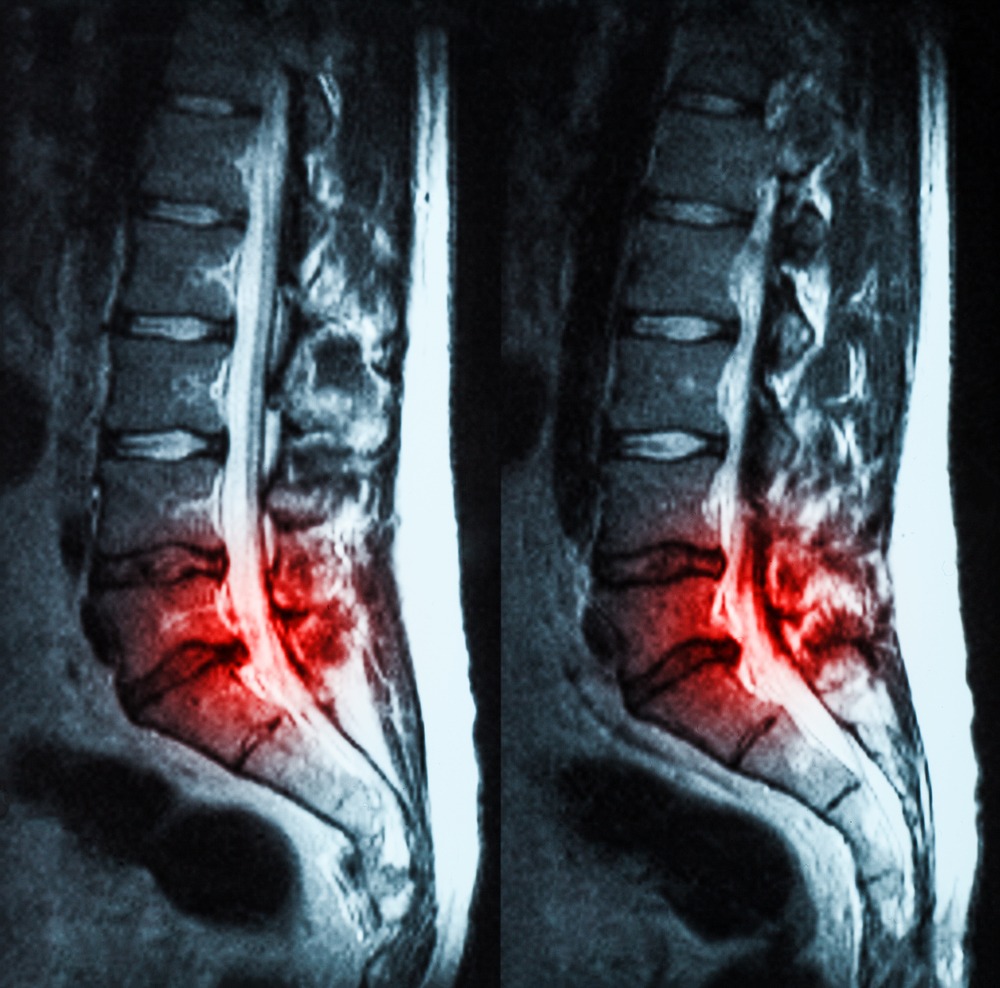

- Rezonans magnetyczny (MRI): Najbardziej precyzyjna metoda obrazowania dysków i struktur nerwowych.

Diagnoza stenozy kanały kregowego

- Dokładna diagnoza jest kluczowa dla wyboru odpowiedniego leczenia.